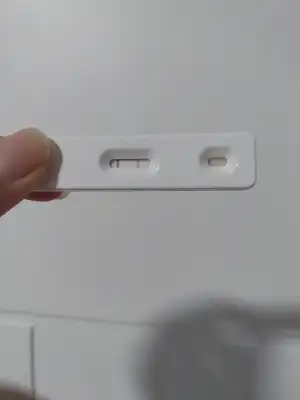

Bir haftadır bel ağrısı göğüs hassasiyeti ve kasıklarımda ağırlık var ve beyaz akıntım var ama idrar testleri negatif. Daha önce psikolojik belirti uydurmuştu bünyem ama en fazla kasık ağrısı oluyordu. Kafayı yiyeceğim artık hamilelik yoksa da regl olmak istiyorum ama hiçbir gelişme yok

hamilelik yoksa da regl olmak istiyorum ama hiçbir gelişme yok

Bir haftadır bel ağrısı göğüs hassasiyeti ve kasıklarımda ağırlık var ve beyaz akıntım var ama idrar testleri negatif. Daha önce psikolojik belirti uydurmuştu bünyem ama en fazla kasık ağrısı oluyordu. Kafayı yiyeceğim artık